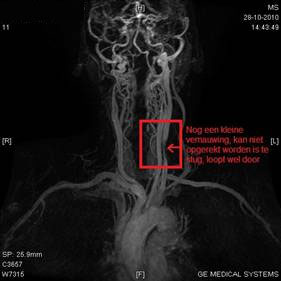

Beythien stemde in met een MRT met contrastvloeistof om op die manier te

kunnen zien of en waar er een eventuele vernauwing zou zitten.

De volgende foto’s spreken weer voor zich, alles zag er bijna goed uit